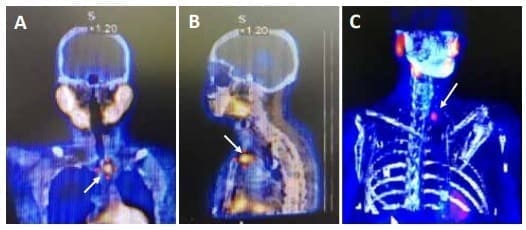

La gammagrafía realizada con Tc99m(tecnecio)-Sestamibi, tanto en imágenes planares como de tomografía computarizada por emisión de fotón único (SPECT, por sus siglas en ingles), tiene utilidad en la localización de adenomas paratiroideos, especialmente en aquellos de tamaño superior a 500 mg 18, 19.

La sensibilidad y la especificidad mejora cuando las imágenes de SPECT son fusionadas con imágenes de la tomografía computarizada (figura 1), preferiblemente adquiridas en equipos híbridos, pasando la sensibilidad de 83 % a 96 % y la especificidad de 80 a 93 %, ventajas más evidentes en adenomas de menor tamaño, de alrededor de 210 mg 20.

Figura 1. Gammagrafía de paratiroides con SPECT-CT que muestra hipercaptación de la

paratiroidea inferior izquierda (flechas blancas).